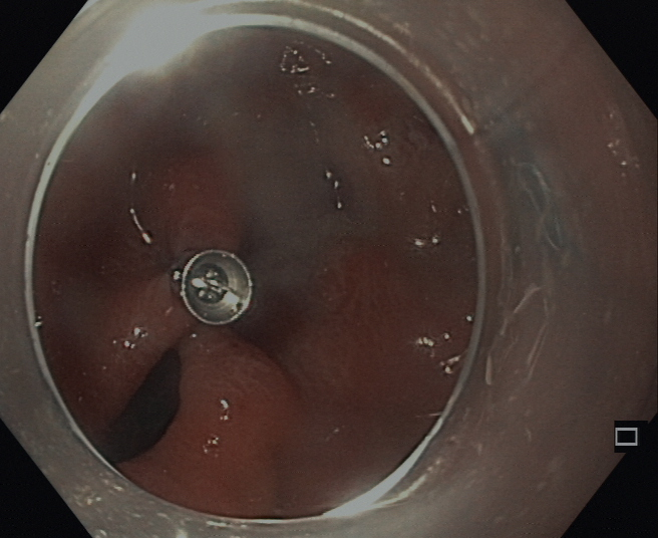

Patienten mit einer bestimmten Erkrankung der Speiseröhre der sog. Achalasie bieten wir nach vorheriger Diagnostik mittels Manometrie  eine Therapie mit der neuen Methode der sog. POEM an.

POEM steht für perorale endoskopische Myotomie des Muskels am Übergang zwischen Speiseröhre und Magen. Dabei wird über einen „Tunnel“ in der Wand der Speiseröhre der Muskel am Mageneingang durchtrennt und anschließend der Tunneleingang wieder verschlossen.

Nach diesem rein endoskopischen Eingriff unter Vollnarkose können Patienten mit einer Achalasie wieder besser Nahrung zu sich nehmen.